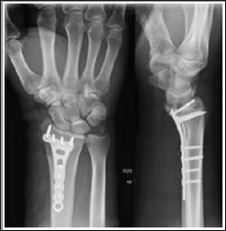

A 48 year-old male, caucasian, policeman, right handed, attended the emergency service due to right wrist pain and functional impotence. Five weeks earlier he had suffered a road accident resulting in a fracture of the distal right radius (AO subtype 23-B3) (Figure 1) and a tibial plafond fracture. At a foreign hospital that received him, he was submitted to radius osteosynthesis with an anatomic volar distal radius plate and in the lower right limb a temporary joint-bridging external fixation was placed during 1 week, and was posteriorly substituted by screws and plate fixation in the tibia and fibula. The wrist cast was removed 4 weeks after surgery in a private hospital in our country. After this episode he began to feel pain, without any history of associated trauma. He had no other previous history of interest. The physical examination revealed a "dinner fork” deformity, with a volar translation of the carpus. The skin was intact. There was no neurovascular deficit. Imaging showed a Dumontier type II volar radiocarpal dislocation (Figure 2A). At the emergency department we conducted closed reduction through traction after infiltration of a local intra- articular anesthetic, without success nevertheless (Figure 2B), so we decided to proceed to surgical treatment. Intraoperatively, through a volar approach of the radius, a bone fragment distal to the plate was visible. A dorsal approach was needed to reduce the dislocation. A radiocarpal fixation with three Kirschner wires was performed, two of them fixing the volar fragment of the distal radius, and one stabilizing the radiocarpal joint. One screw of the plate was removed due to its' intraarticular location. The distal radioulnar joint was evaluated under dynamic fluoroscopy and was apparently stable. Immediate postoperative radiographs confirmed a concentric reduction and stable fixation of the radiocarpal joint (Figure 3). Postoperatively, the patient was placed in an arm cast with free elbow and metacarpophalangeal (MP) joints. There were no perioperative complications. The immobilization and the kirschner wires were maintained for 7 weeks. After removing the cast and the kirschner wires, the patient presented flexion of 20°and extension of 15°, which improved up to flexion 30° and extension 60°, supination 60°, with preserved pronation, 24 months after the trauma. At this time, the patient reports no pain, feeling of instability or signs of nerve compression. The DASH disability score result was 3,1 and the Mayo Wrist Score was 93. The radiograph control did not show any relevant alteration (Figure 4).

Figure 4: Radiographic and clinical results after 24 months. AP view and lateral view (A); Comparative photographs of both hand in flexion, extension, pronation, supination (B).